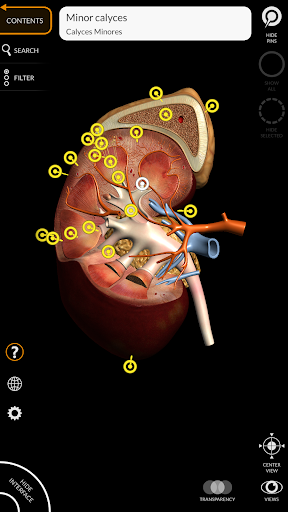

"Anatomy 3D Atlas" дозволяє легко та інтерактивно вивчати анатомію людини.

Завдяки простому та інтуїтивно зрозумілому інтерфейсу можна спостерігати кожну анатомічну структуру під будь-яким кутом.

Анатомічні 3D-моделі особливо деталізовані та мають текстури з роздільною здатністю до 4k.

АНАТОМІЧНІ 3D МОДЕЛІ

• Сечостатева система (чоловіча та жіноча)